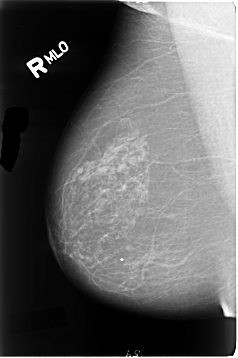

Digital Database for Screening Mammography

Volume: cancer_01 Case: B-3081-1

B_3081_1.RIGHT_MLO

DATE_OF_STUDY 18 10 1994

PATIENT_AGE 71

FILM_TYPE REGULAR

DENSITY 2

RIGHT_CC LINES 4672 PIXELS_PER_LINE 2816 BITS_PER_PIXEL 12 RESOLUTION 50 NON_OVERLAY

RIGHT_MLO LINES 4648 PIXELS_PER_LINE 3088 BITS_PER_PIXEL 12 RESOLUTION 50 NON_OVERLAY